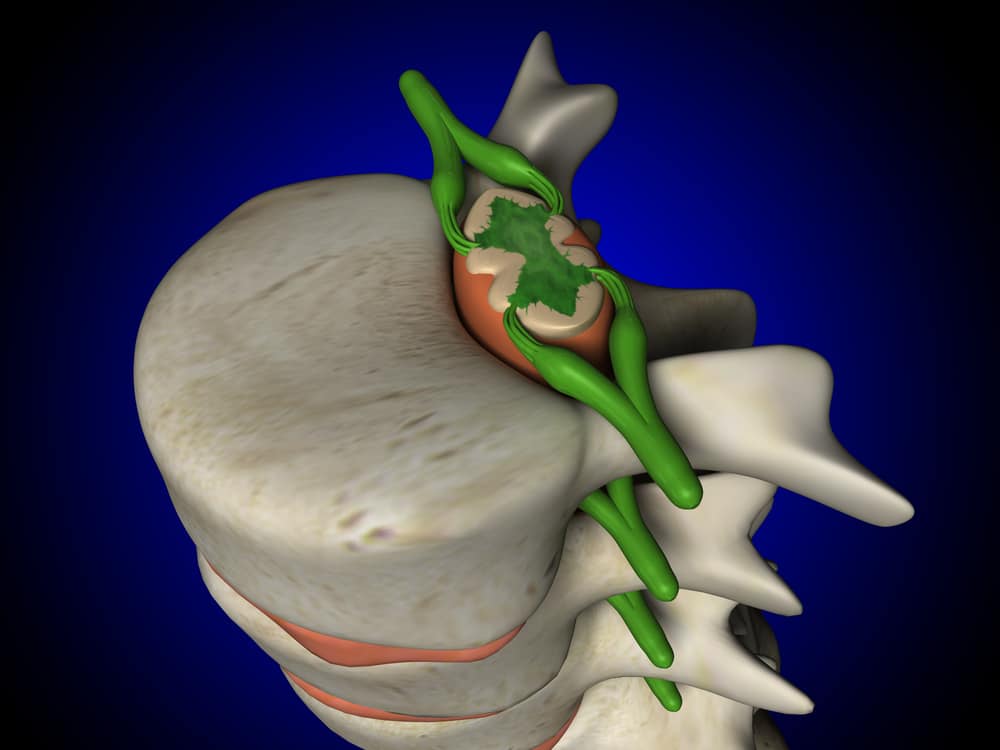

Konsep Cedera Sumsum Tulang Belakang Foto Stok Unduh Gambar Sekarang Istock

Konsep Cedera Sumsum Tulang Belakang Foto Stok Unduh Gambar Sekarang Istock